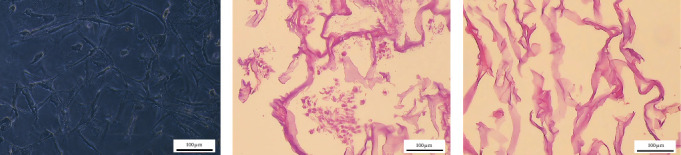

背景:基于干细胞的再生方法已经发展到治疗骨关节炎(OA)和修复软骨缺损。在本研究中,我们利用人Wharton’s jelly-derived mesenchymal stem cells (hWJ-MSCs)构建了一个三维(3D)胶原基脱细胞生物支架,并分析了其再细胞化和随后向软骨细胞分化的潜力。方法:从人华氏水母中分离MSCs,采用流式细胞术进行鉴定,并向成骨和成脂谱系分化。在3D胶原支架中培养hWJ-MSCs。细胞沉积基质后,对支架进行脱细胞处理,培养新的hWJ-MSCs并向软骨细胞分化。通过苏木精和伊红(H&E)染色、DNA定量、扫描电镜(SEM)和拉曼光谱来评估脱细胞过程的效率。对软骨形成标志物(包括II型胶原、聚集蛋白和骨连接蛋白)进行免疫组化和转录评价。结果:制备的脱细胞支架与完整支架相比,核酸物质含量极低。用扫描电镜验证了脱细胞过程的完整性和效率。此外,完整和去细胞支架的拉曼光谱比较表明,碳水化合物、脂质和DNA含量显著降低。在软骨培养基中再细胞化三周后,与阴性对照组相比,特定软骨细胞标志物(包括II型胶原、聚集蛋白和骨连接蛋白)的免疫反应性和表达水平显著增加。结论:hWJ-MSCs及其在制备无核酸3D胶原基支架中的应用为研究细胞外基质(ECM)如何促进特定细胞微环境提供了一种有前景的体外模型。脱细胞的ECM还可以用于开发用于再生医学的新型无细胞生物医学产品。

Background: Stem cell-based regenerative approaches have been developed to treat osteoarthritis (OA) and repair cartilage defects. In the present study, we fabricated a three-dimensional (3D) collagen-based decellularized biological scaffold using human Wharton's jelly-derived mesenchymal stem cells (hWJ-MSCs) and analyzed its recellularization and subsequent differentiation potential toward chondrocytes. Methods: MSCs were isolated from human Wharton's jelly, characterized by flow cytometry, and differentiated toward osteogenic and adipogenic lineages. hWJ-MSCs were cultured in a 3D collagen scaffold. After the matrix was deposited by the cells, the scaffold was decellularized, and new hWJ-MSCs were cultured and differentiated into chondrocytes. The efficiency of the decellularization process was assessed using hematoxylin and eosin (H&E) staining, DNA quantification, scanning electron microscopy (SEM), and Raman spectroscopy. Immunohistochemical and transcriptional evaluation of chondrogenic markers, including collagen type II, aggrecan, and osteonectin, was performed. Results: Prepared decellularized scaffolds showed very low levels of nucleic materials compared to intact ones. The integrity and efficiency of the decellularization process were confirmed using SEM. Moreover, a comparison of Raman spectra of intact and decellularized scaffolds demonstrated a remarkable reduction in carbohydrate, lipid, and DNA content. Three weeks after recellularization in the presence of chondrogenic medium, the immunoreactivity and expression levels of specific chondrocyte markers, including collagen type II, aggrecan, and osteonectin, significantly increased compared to negative controls. Conclusion: hWJ-MSCs and their use in fabricating nucleic acid-free 3D collagen-based scaffolds represent a promising in vitro model for investigating how the extracellular matrix (ECM) contributes to specific cell microenvironments. Decellularized ECM can also be utilized to develop novel, cell-free biomedical products for regenerative medicine.